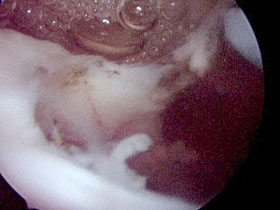

Man unterscheidet zwischen inkompletten und kompletten

Rupturen, wobei die inkompletten Risse mehr gelenkseitig gelegen

sein können und als sogenannte A-Rupturen bezeichnet werden

oder mehr bursaseitig liegen und dann als sogenannte B-Rupturen

gelten.

Ist die Ruptur komplett, kann sie eine, zwei oder drei Sehnen betreffen.

Die häufigste Rissform lokalisiert sich an der Supraspinatussehne

und findet sich in Form einer L-förmigen oder einer halbmondförmigen

Läsion.

Abbildung:

L-förmige und halbmondförmige Läsion |